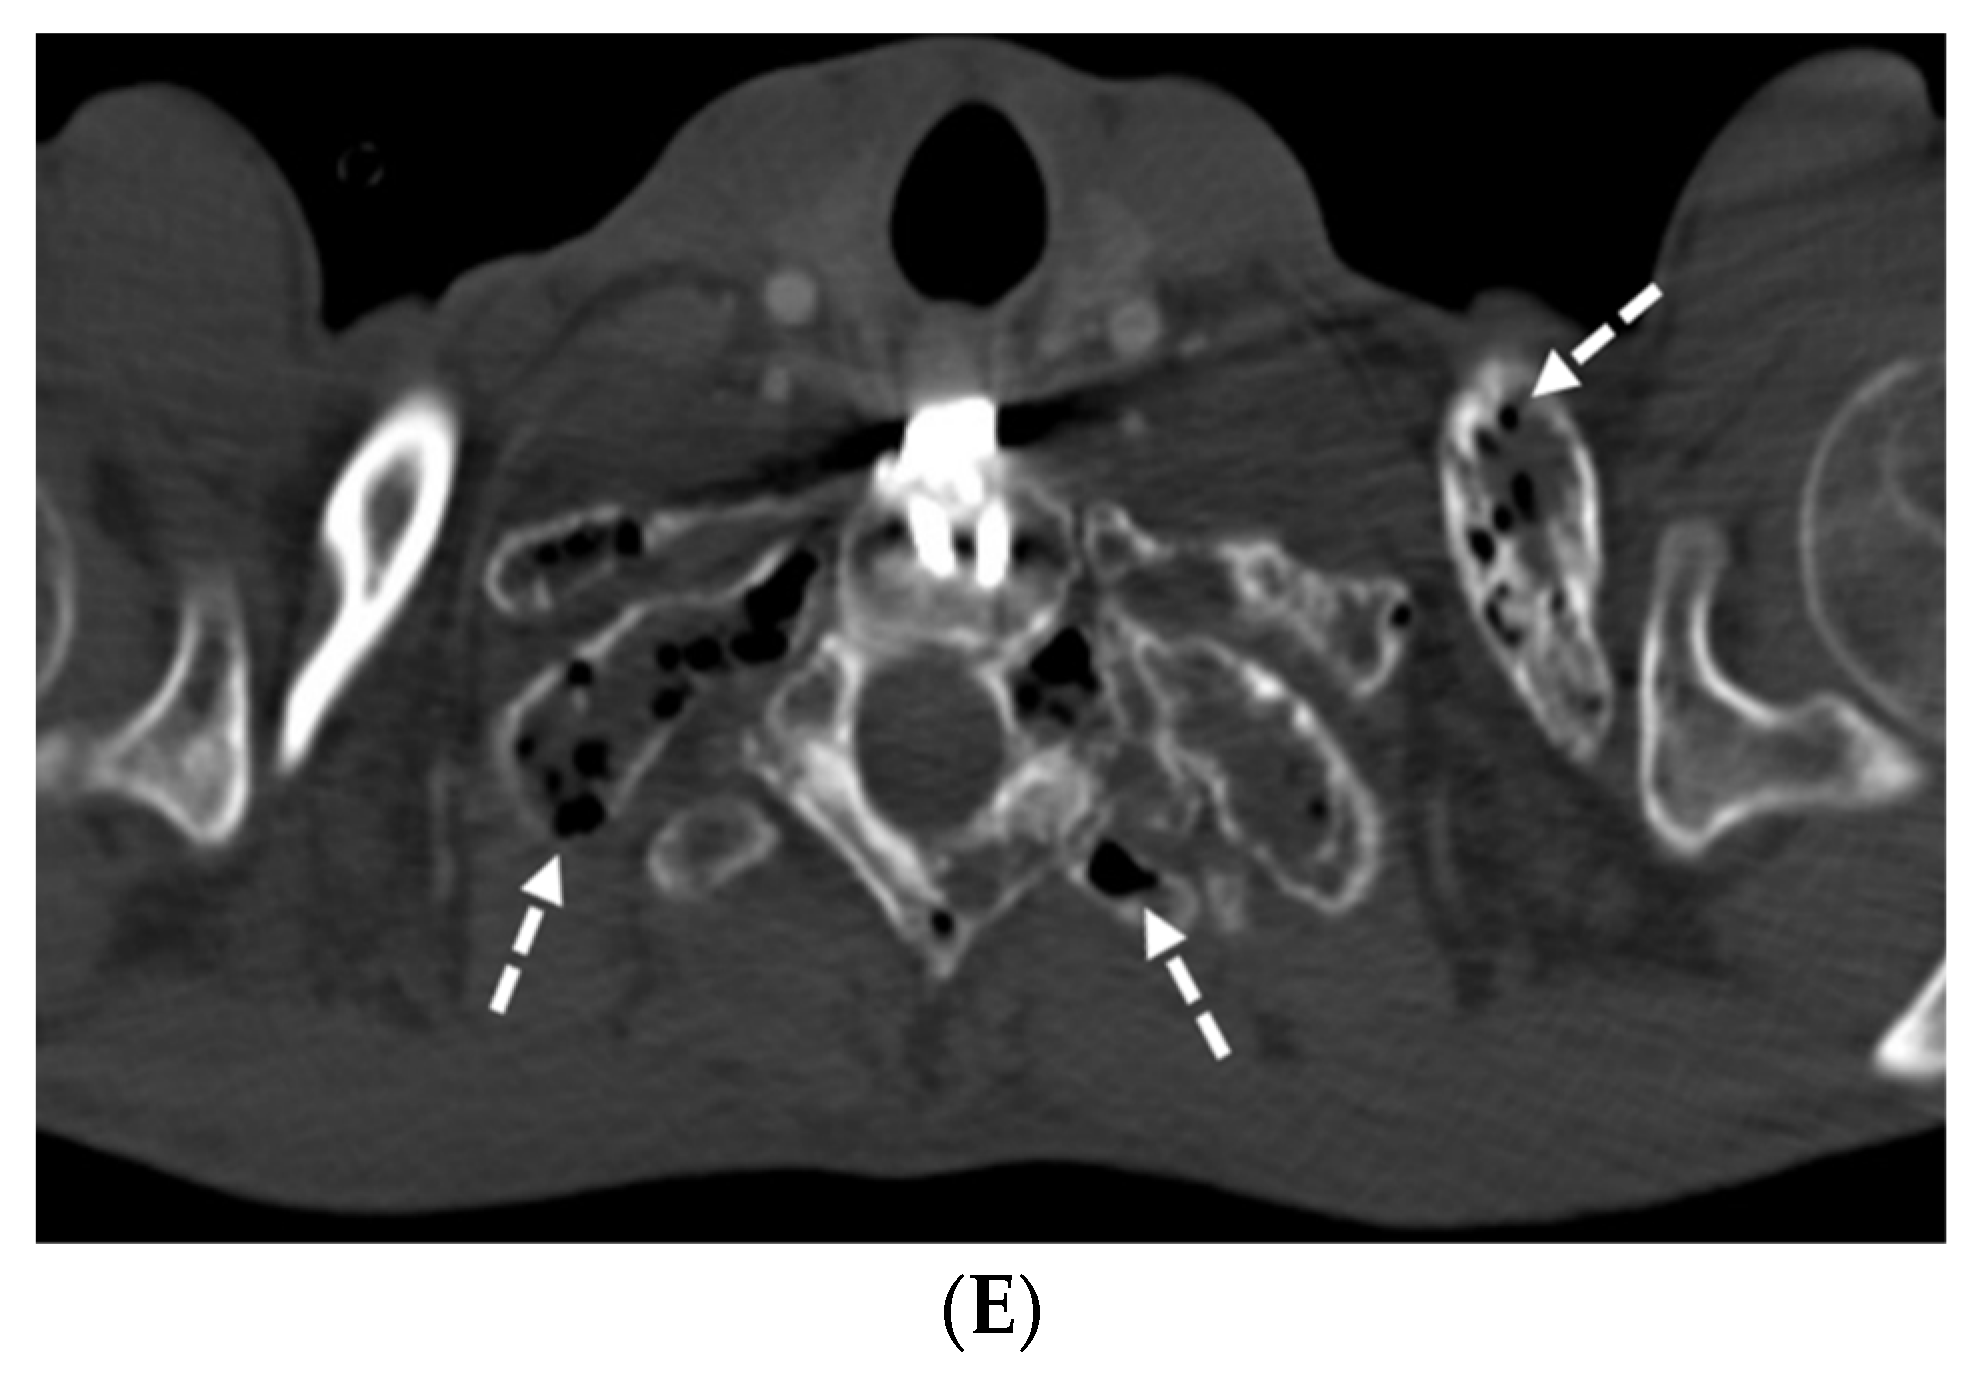

| Silicone embolization | History of illegal cosmetic injection of liquid silicone | Multiple subcutaneous soft tissue attenuation nodules, sometimes with peripheral calcification or surrounding fat stranding |